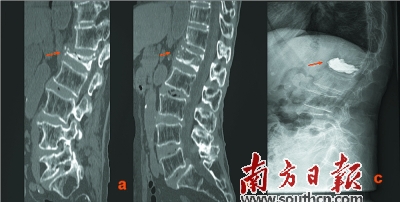

治療前后對(duì)比:a為治療前,b為手法復(fù)位后,c為手法復(fù)位+PKP術(shù)后。

梁木榮說(shuō):“該患者年紀(jì)大、腰椎壓縮程度重,受壓縮的椎節(jié)被壓扁得只剩下1/4,極大地增加了該手術(shù)的難度,很多醫(yī)生都措手無(wú)策。”而胡方煜醫(yī)生卻具有豐富的臨床經(jīng)驗(yàn),他采取了中西醫(yī)結(jié)合的辦法,先對(duì)患病椎體行手法復(fù)位,復(fù)位成功后,再進(jìn)行PKP手術(shù)。

“手術(shù)很順利,術(shù)后吳婆婆的腰背痛明顯減輕,術(shù)后就可以下地走路啦,”梁木榮說(shuō)。手術(shù)第2天,吳婆婆帶著定制的支具就出院了。